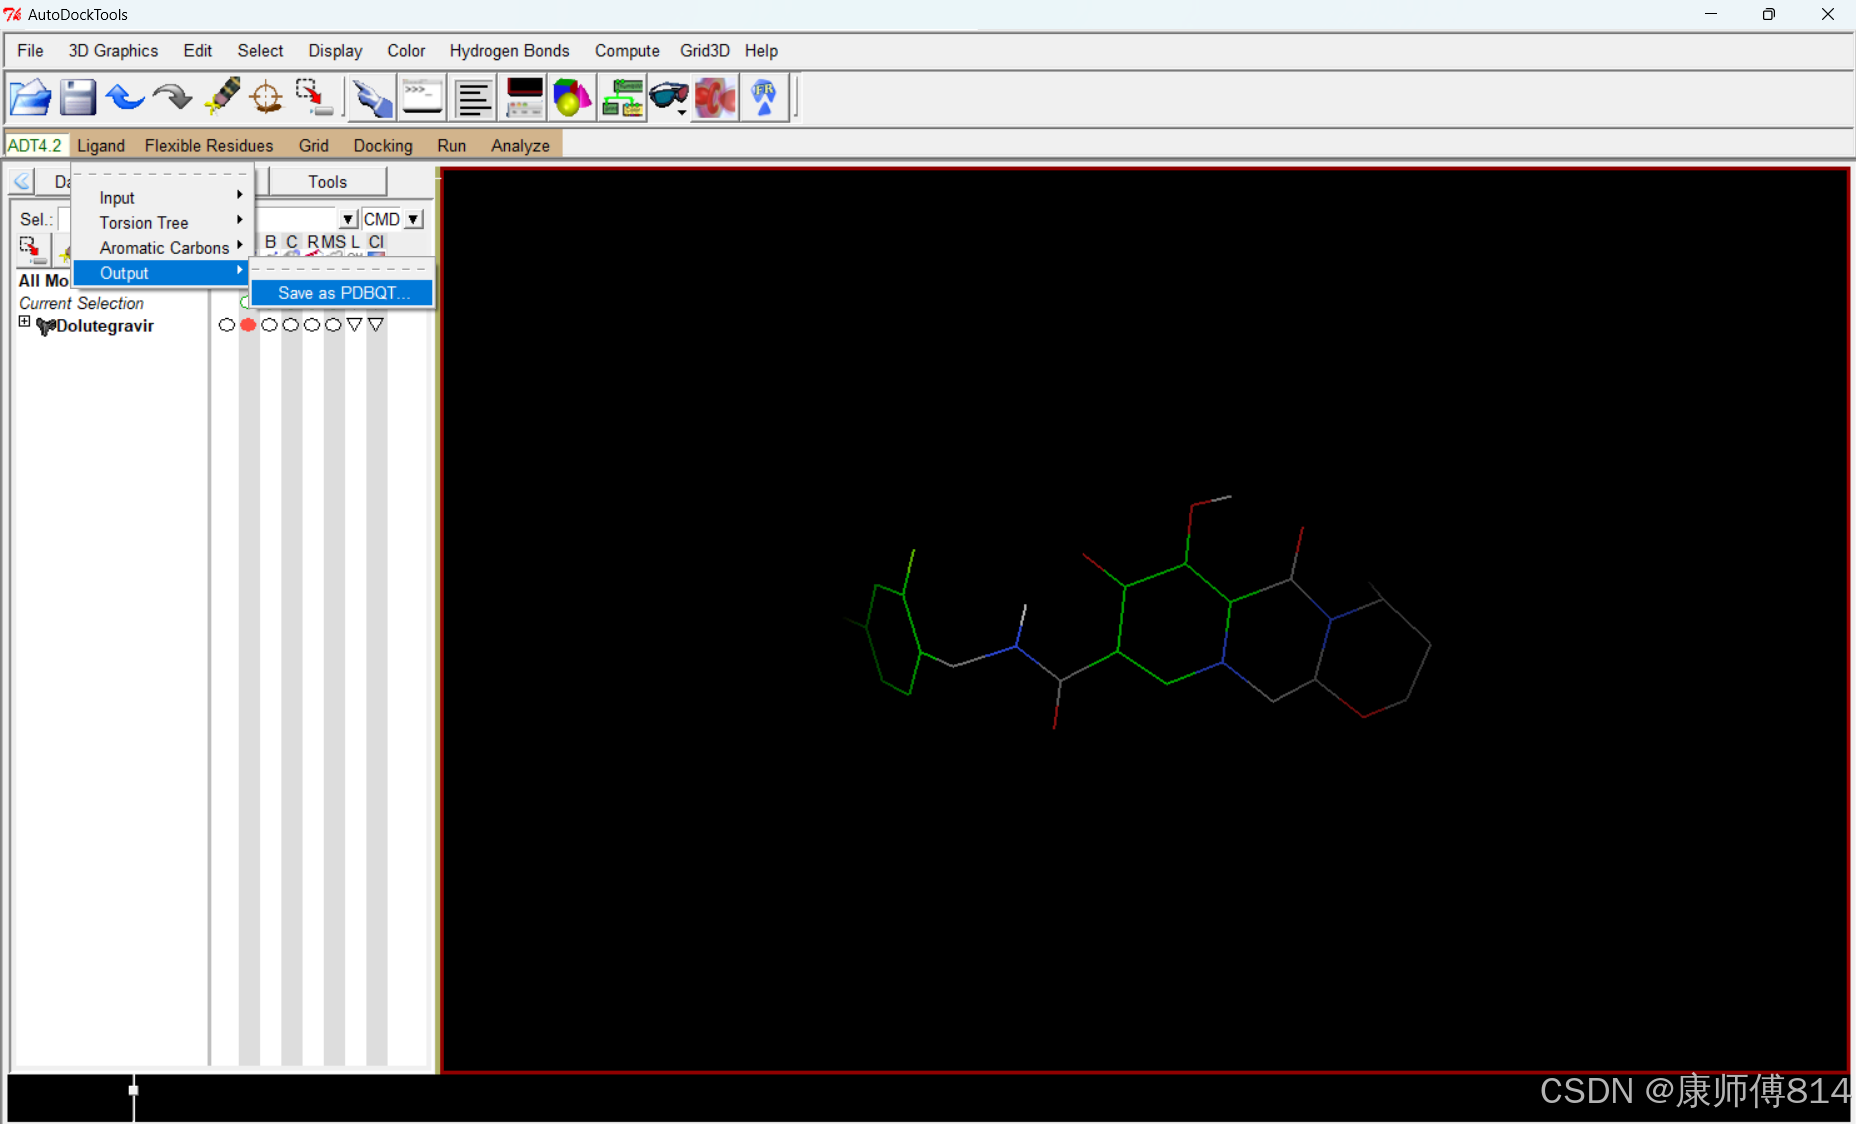

#选择小分子为配体

#点击Ligand-Input-Choose,点击小分子名称,点击Select Molecule for Autodock4,点击Ligand-Output-Save as PDBQT,保存为pdbqt文件